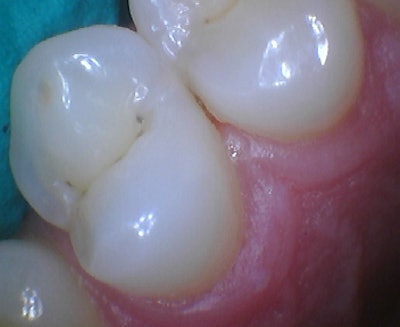

Figure 2: Pre-operative intraoral photo.

Figure 5: Restoring adjacent Lesions with the Halo Matrix, which show adequate contour and great sealing at the gingival margin.

Figure 6: Direct final restorations after polish. Note the adequate contours and broad contact zone.